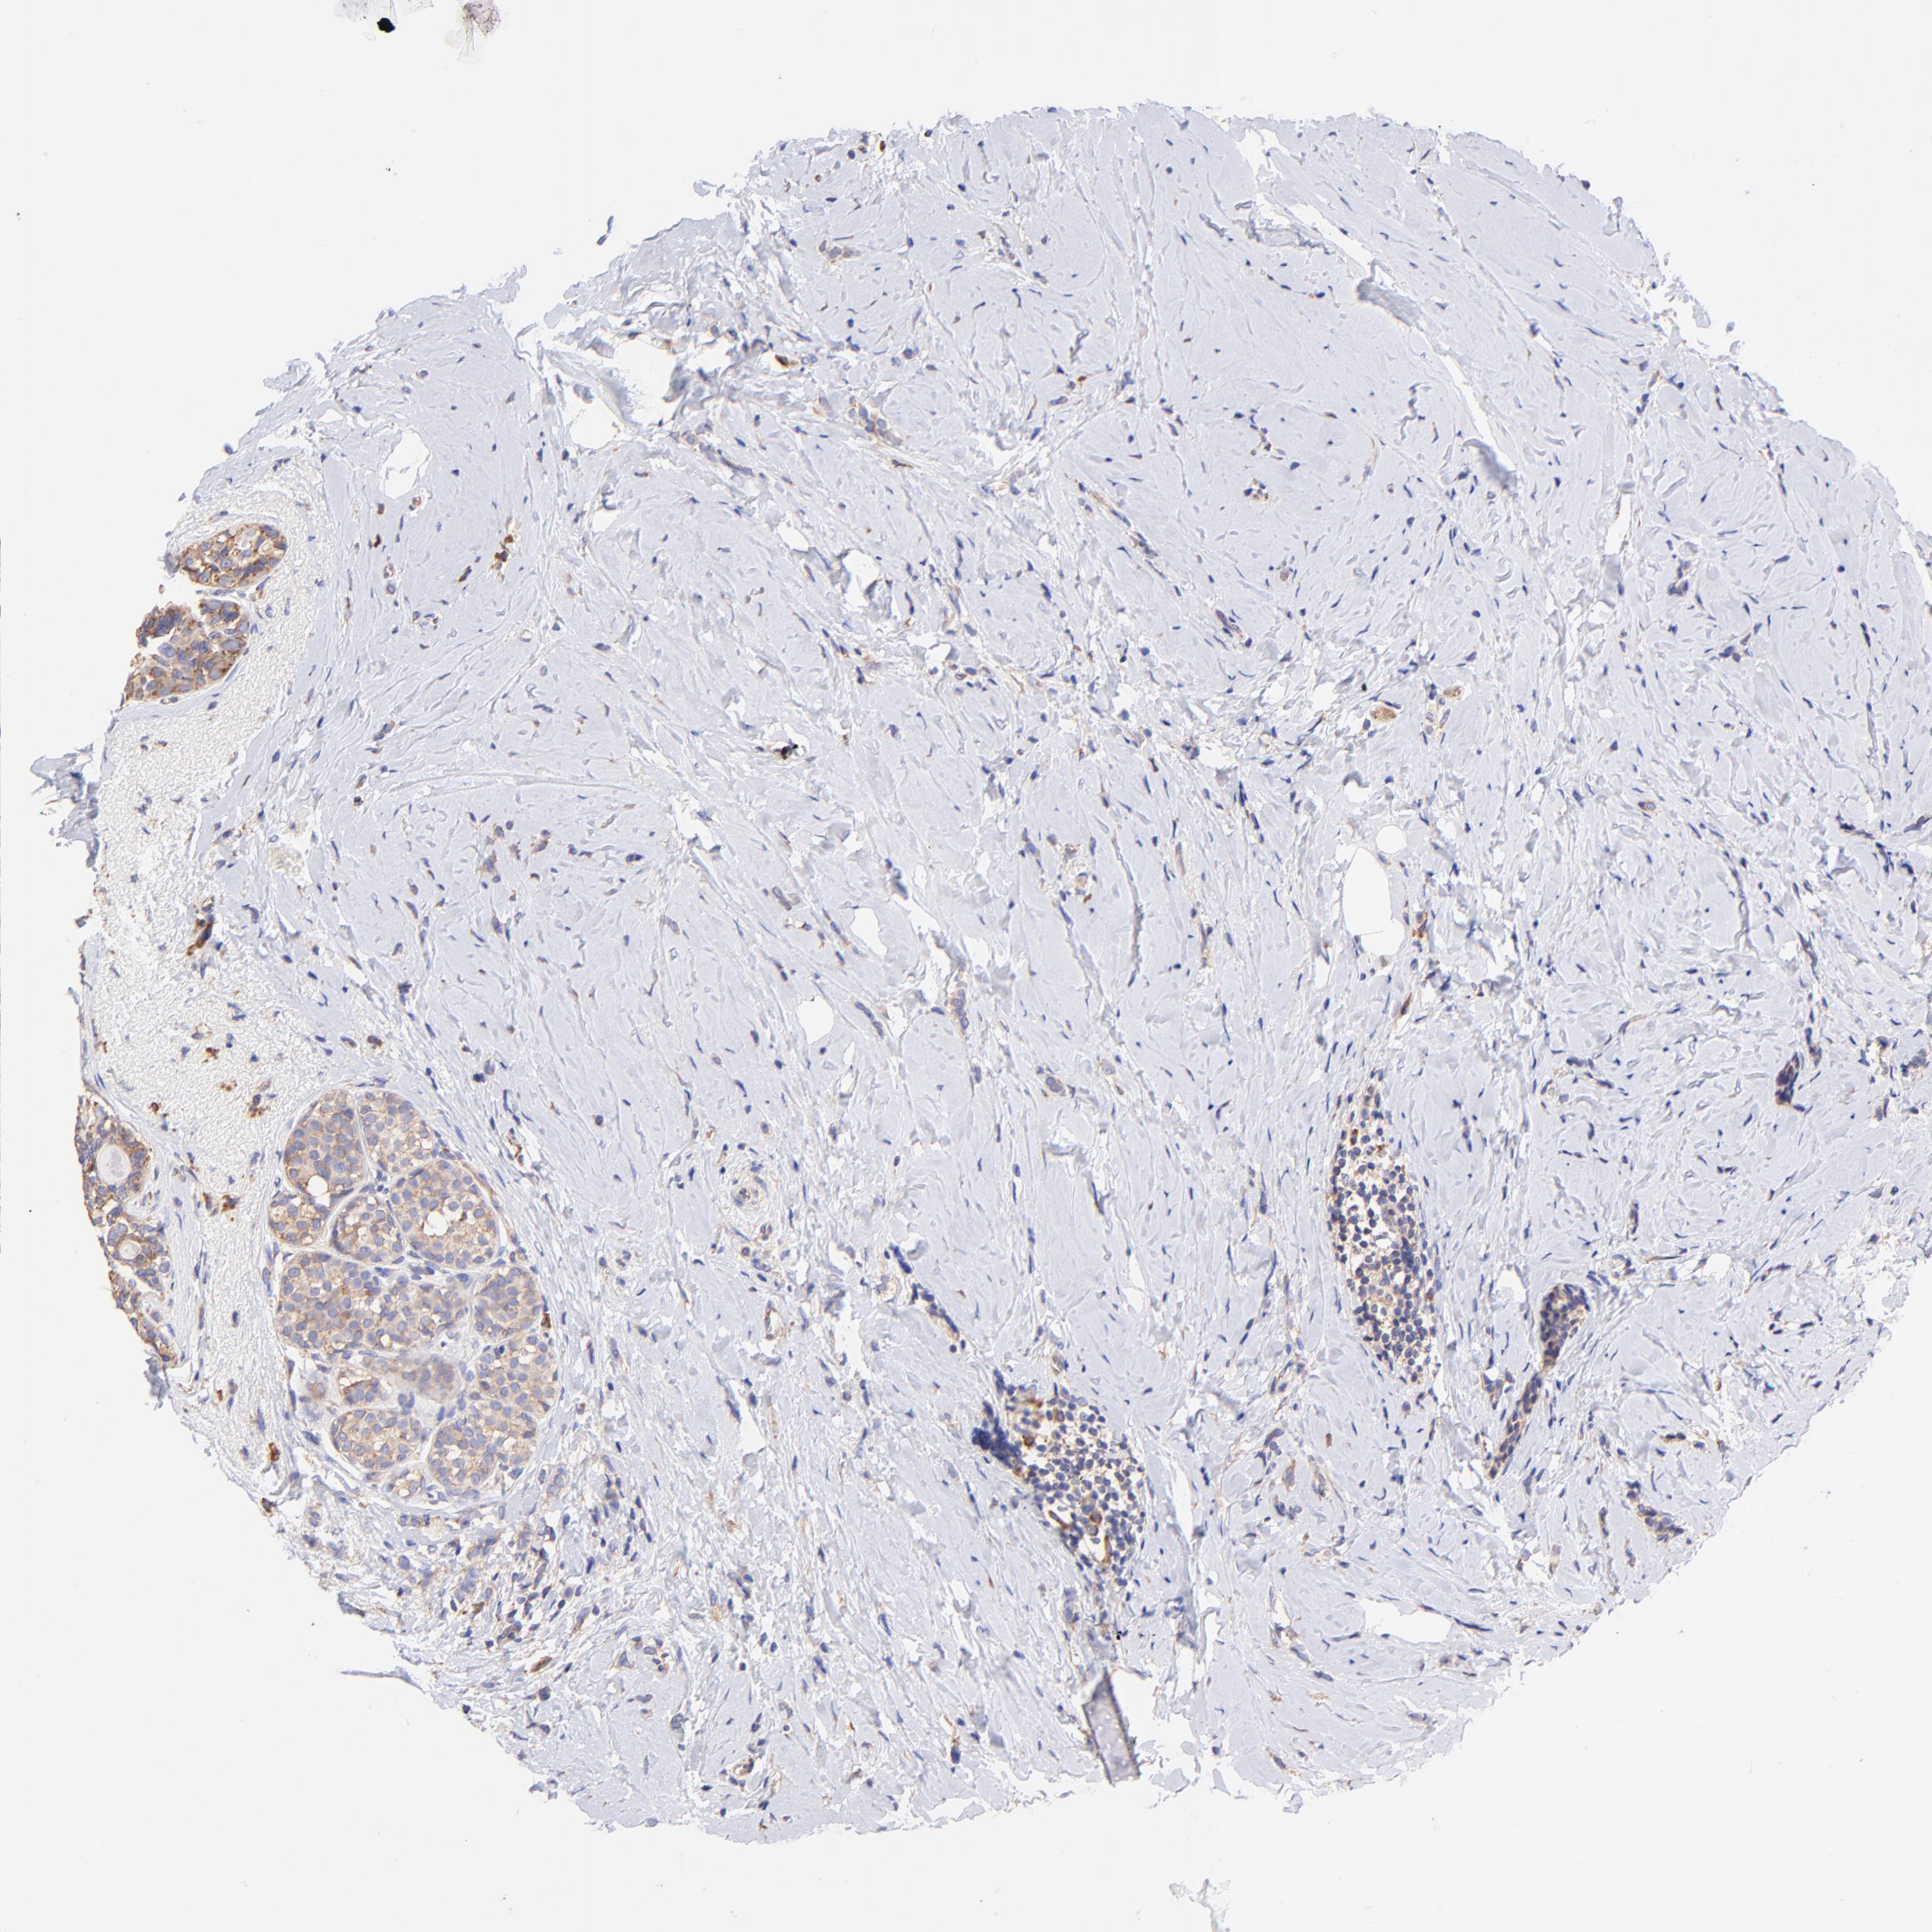

BRCA TCGA BRCA VALIDATION PROTEIN EXPRESSION

ANTIBODIES

AND

VALIDATION